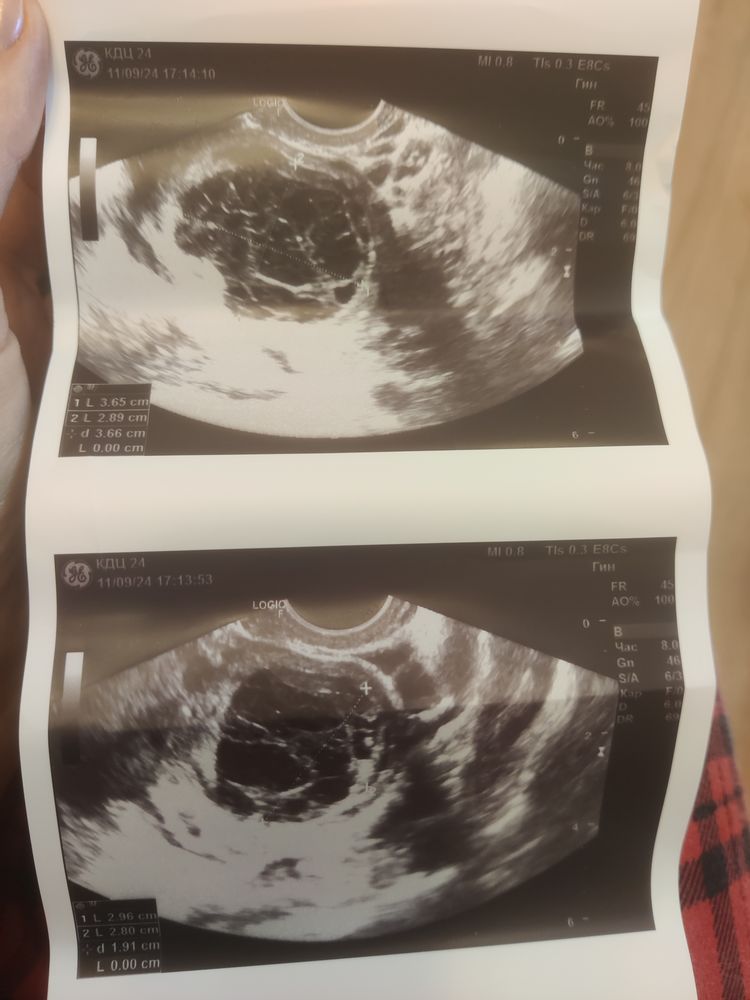

Может быть кто то разбирается и сможет определить что за вид кисты это? Хотелось бы знать была ли овуляция. Врач точно ответить не смогла

Очевидно- киста жёлтого тела. Внутри - рыбацкая сеть ( это нити фибрина).

Многокамерная киста яичника. У Вас точно хороший врач? Я бы забила тревогу.

Структура на классическую фолликулярную не похожа, тут многокамерная какая-то. По картинке невозможно сказать, нужно смотреть кровоток и структуру по нескольким срезам